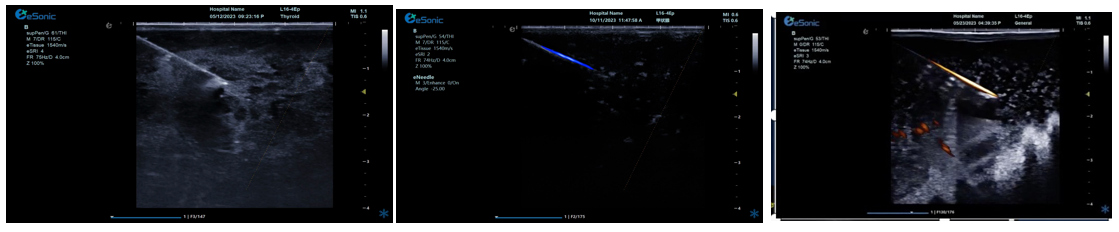

NeedleTS?穿刺针智能解决方案

?穿刺针增强显影?智能MAP?无磁导航

为临床医生有创穿刺保驾护航,真正实现精准导航。